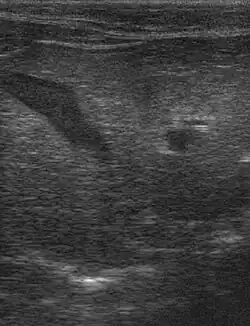

Bei der Sonographie zeigt sich in der Leber eine diffuse echoreiche Verdichtung.